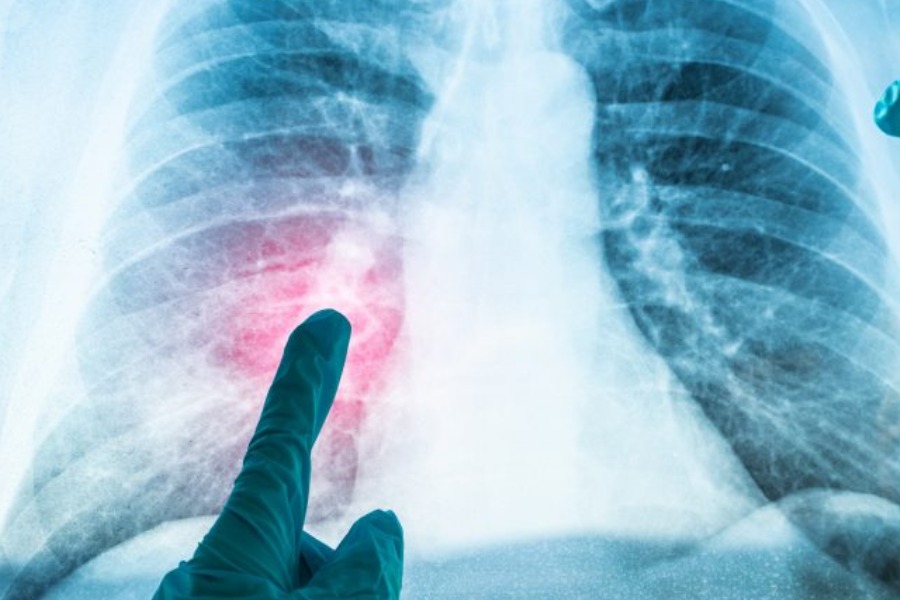

Câncer no pulmão | Foto: Reprodução/Internet

Radiografias de tórax revelaram um quadro de quilotórax, caracterizado pelo acúmulo de líquido leitoso entre as camadas que revestem os pulmões, chamadas de pleuras. Isso acontece quando o sistema linfático, responsável por drenar o excesso de fluidos do corpo, é interrompido.

Exames mais detalhados mostraram um tumor benigno comprimindo os pulmões. O caroço tinha 7 cm e pressionava o ducto torácico — um importante vaso linfático — impedindo que o fluido saísse do corpo.